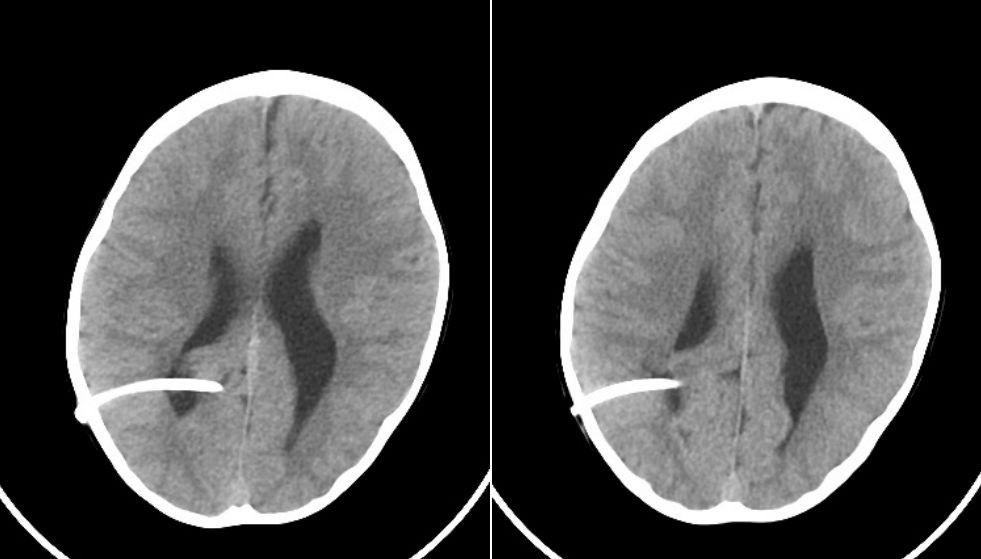

病例2:术后1天复查CT:前囟门较前平坦。

术后1年半(2014.5.16)复查CT:脑室形态较前好转缩小,脑实质发育良好。

术后2年半(2015.7.23)复查CT:较前相仿。

术后4年复查(2016.12.29)CT:较前相仿。